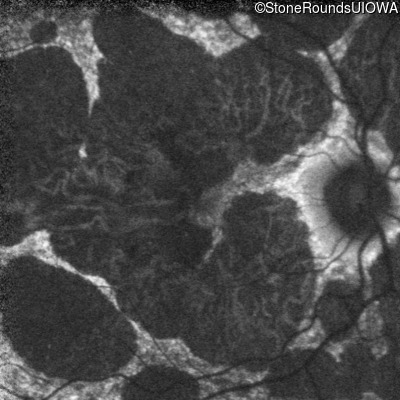

Age at visit: 51 years

This 51 year old woman first experienced some abnormality in her distance vision when she was 27 years old. She feels that her vision has been stable since that time.

Diagnosis & molecular findings

AR Stargardt Disease ABCA4 Gly1507Arg GGG>AGG IVS42+1 G>A AR